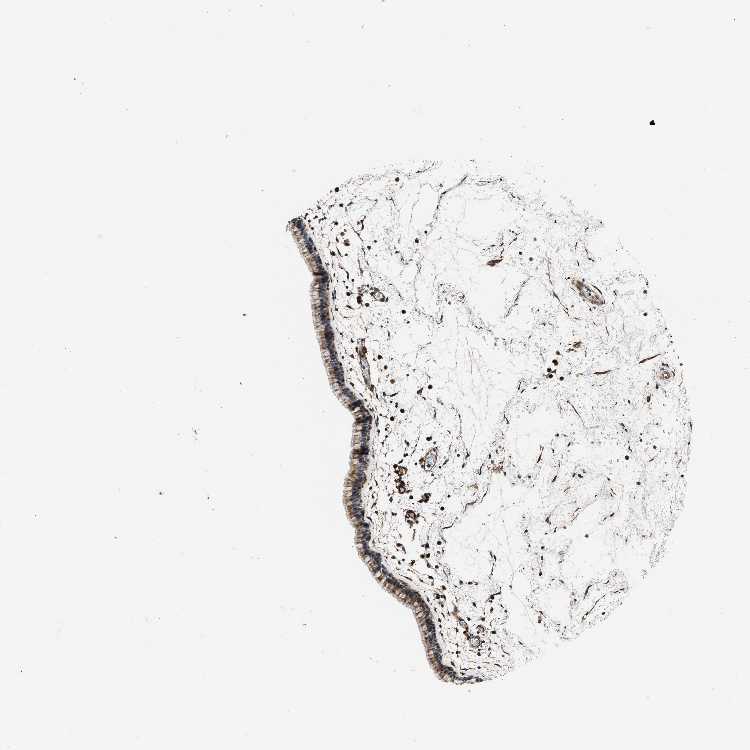

TISSUE PRIMARY DATA NASOPHARYNX Show tissue menu

NASOPHARYNX - Antibody stainingi

Antibody staining in the annotated cell types in the current human tissue is reported as not detected, low, medium, or high, based on conventional immunohistochemistry profiling in selected tissues. This score is based on the combination of the staining intensity and fraction of stained cells.

Each image is clickable and will lead to virtual microscopy that enables deeper exploration of all samples and also displays staining intensity scores, fraction scores and subcellular localization as well as patient and tissue information for each sample.

Antibody HPA019885Antibody CAB026255

Respiratory epithelial cells MediumMedium